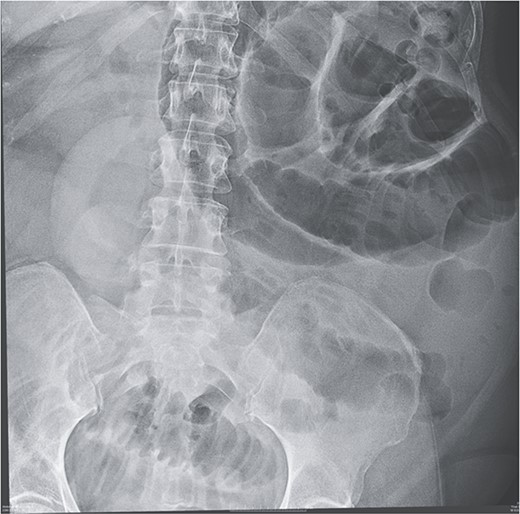

Given her abdominal symptoms and signs, she was subjected to an abdominal X-ray (Fig. 1), which showed multiple distended loops of the small bowel, and a chest X-ray, which showed left basal atelectasis. A working diagnosis of SBO was made. She was put nil by mouth. A nasogastric tube and a urinary catheter were inserted. After initial resuscitation, she was subjected to CTAP with contrast. The findings of the CTAP were in keeping with acute distal SBO secondary to an ileo-ileal intussusception. No obvious mucosal mass was stated in the initial report (Figs 2 and 3).